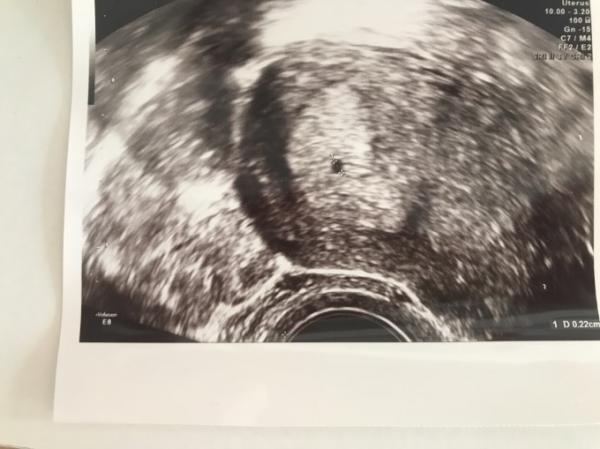

Hallo ihr Lieben, nachdem ich jetzt doch recht viel im Forum gelesen habe, stellen sich mir doch noch einige Fragen, die mich sorgen. Mein Ultraschall ( FA meinte 5 Woche, mein Zyklus war sehr lang, Test am 29.9 noch negativ, Schwangerschaft war eine riesige Überraschung) zeigte nur einen schwarzen Punkt mit einem Durchmesser von 0,22cm also 2,2 mm. Sie meinte das ist normal und in zwei Wochen sieht man mehr. Ich lese aber, dass es bei allen größer ist in der 5 Woche? Ich leider nicht an Übelkeit, aber hab einfach keine „Lust zu essen“. Nix macht mich an! Das einzige was geht ist Knäckebrot und Käse und Kekse. Ich zwing mich mal n grünen Smoothie zu trinken. Aber Fleisch und Fisch und fettiges löst ein „nicht gut“ Gefühl aus. Symptome die ich habe sind extremes Brustspannen, bisschen Kreislauf morgens und Herzraseb beim Trepppen gehen. Am Anfang hatte ich extremes ziehen im Unterleib, ist aber vorbei. Momentan nur noch ein leichtes stechen hier und da. Habe einfach Angst, da ich mich so unschwanger fühle, dass es längst vorbei ist, ohne dass ich es gemerkt habe. Können sich Symptome ändern? Ist es schlimm, dass ich gerade nicht so viel und ausgewogen essen? Wie geht ihr mit euren sorgen um? Mein freund ist schon ganz traurig, weil ich mich nicht freue. Ich hab einfach so Angst :( Bild ist im Anhang! Über Antworten freue ich mich! Liebe Grüße

Bild zu Erste Schwangerschaft, einige Unsicherheiten - Schwanger - wer noch? Rund um die Schwangerschaft